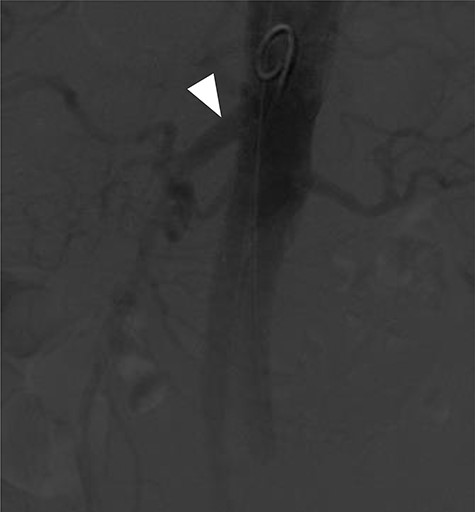

A 78-year-old gentleman admitted for elective FEVAR to treat his CT confirmed 5.7 cm juxtarenal AAA. He was not suitable for open repair and initially offered the option of no intervention due to ongoing comorbidities resulting in poor cardiopulmonary function; however, he was keen to proceed with surgery. From pre-implant planning CT angiogram (CTA), infrarenal endograft was unsuitable for EVAR due to reverse conicity and unhealthy infrarenal aortic neck (Fig. 1); therefore, FEVAR was chosen. RRHA from SMA was also seen in pre-operative CTA but not reported (Fig. 2).

Pre-implant planning CTA showing unhealthy infrarenal aortic neck.